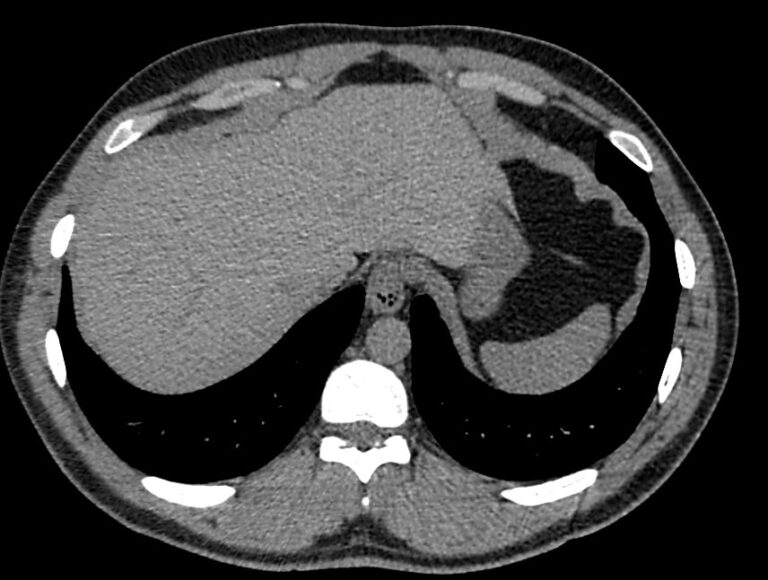

Печеночная ткань имеет обильное кровоснабжение, поэтому часто ультразвуковая диагностика заболеваний печени затруднена. Одним из наиболее информативных методов диагностики является мультиспиральная КТ печени, которая может проводиться в стандартном режиме и с внутривенным болюсным контрастированием. Введение йодсодержащего контрастного вещества значительно повышает диагностическую ценность компьютерной томографии и позволяет, в частности, выявить злокачественное образование на ранней стадии, отличить доброкачественный процесс от злокачественного, визуализировать изменения внутрипеченочных желчных протоков и многие другие патологические процессы.

В нашей клинике сканирование печени выполняется на современном 128-срезовом томографе экспертного класса TOSHIBA AQUILION CXL, который производит послойное сканирование исследуемого органа с последующей цифровой обработкой полученных данных для создания трехмерных изображений печени высокого качества и контрастности. Увеличенное количество детекторов, вмонтированных в аппарат, обеспечивает быстрое время исследования и пониженные дозы рентгеновского излучения, получаемого пациентом.

Обследование печени посредством компьютерной томографии позволяет выявить следующие патологии:

- первичные опухоли и метастазы;